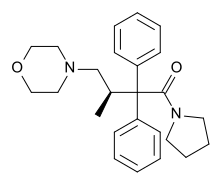

Beta-Amino Ketones

Diphenylmethylpiperazines